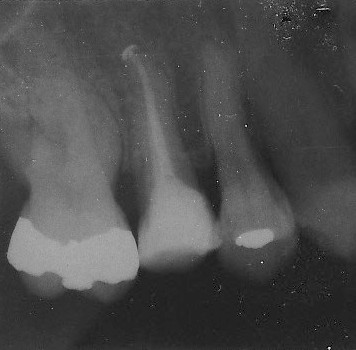

Im Inneren des Zahnes befindet sich ein Höhlensystem, in dem sich Nerven und Blutgefäße befinden. Wenn eine Karies sich von außen bis zu dieser Höhle vorangearbeitet hat, kann sich der Zahnnerv (Pulpa) in einem meist schmerzhaften Prozess entzünden. Ein Absterben des Nervs ist die Folge.

Um den Zahn dauerhaft zu erhalten und ein Fortschreiten der Entzündung in den Knochen zu verhindern, wird das erkrankte entzündete Gewebe aus dem Hohlraum entfernt. Nach dem mechanischen Erweitern der Kanäle, um infizierte Zahnhartsubstanz von den Wänden abzutragen wird durch gewissenhaftes Spülen mit hochwirksamen desinfizierenden Spüllösungen immer mehr Keimfreiheit erreicht. Alle Arbeitsschritte erfolgen durch ein kleines Loch in der Kaufläche des Zahns und werden mit Hilfe der Lupenbrille durchgeführt.

Wenn der Zahn schließlich absolut symptomfrei und beim Kauen wieder gut belastbar ist, wird das Kanalsystem neu gefüllt und der Zahn mit einer dichten adhäsiven Füllung versorgt, so dass sicher keine neuen Keime eindringen können.

Das Erreichen der richtigen Länge der Wurzelkanäle ist von großer Bedeutung für den Behandlungserfolg - für größtmögliche Genauigkeit stehen uns hierfür Messgeräte zur Verfügung, die über Widerstandsmessungen genau die Stelle des Übergangs von Wurzelkanal zu umgebendem Gewebe anzeigen können. Leider übernimmt die gesetzliche Krankenkasse weder diese Messgeräte noch die Anwendung von Spüllösungen oder Ultraschallgeräten zur effektiven Keimreduktion. Trotzdem bieten wir Ihnen diese Behandlungsmöglichkeiten gerne an, denn auch uns ist der Erfolg der Wurzelkanalbehandlung wichtig, die immerhin die letzte Möglichkeit ist, den eigenen Zahn langfristig zu erhalten. Aufwändige Rekonstruktionen mit Implantaten oder Brücken sind so in vielen Fällen vermeidbar.